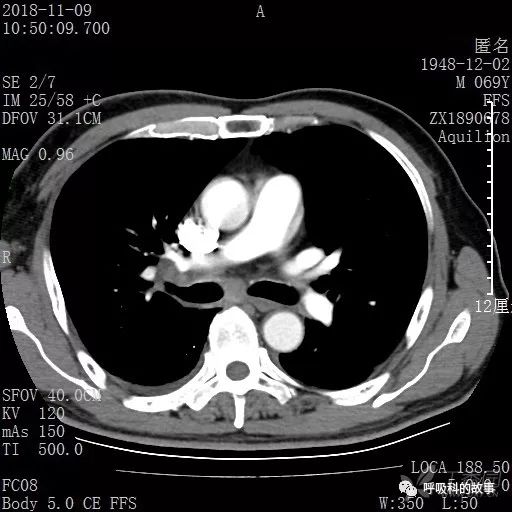

胸部增强CT示右肺门占位伴远端阻塞性肺炎,纵膈、右肺门、右侧颈根部、右侧腋下及肝门部肿大淋巴结。两侧胸腔少量积液。

纵隔窗的增强CT